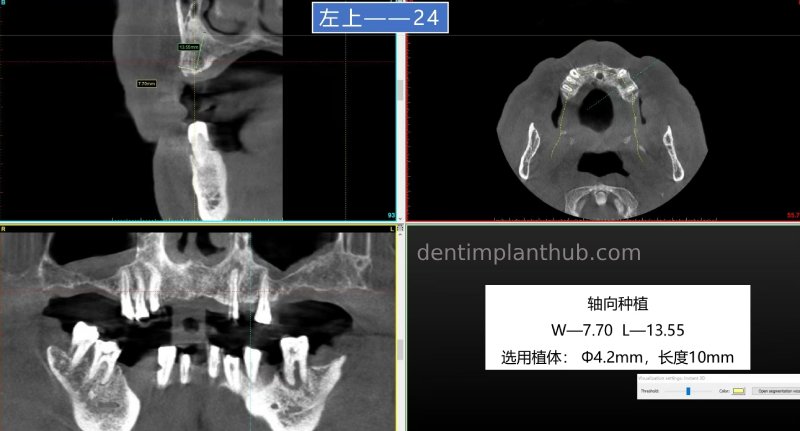

24, normal implantation, subsequent restoration can be done together with 12, 22 for a consecutive crown;

23, immediate extraction with implant model 3810;